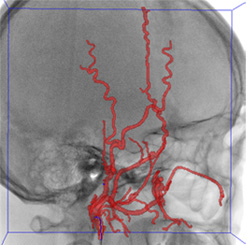

• 实时引导线跟踪使用C-Arm成像设备

• 可视化跟踪移动对象是计算机视觉领域重要的开放问题之一因问题复杂性而非通用性,只考虑定义清晰应用的解决方案生物医学领域视觉跟踪常以传输或投影获取模型为基础,使现有程序不适用,因为与常用获取模型不相容利用专门适应获取模型的方法可以取得更好的结果。

最小入侵内向干预是外科手术的好例子,如果没有适当的成像设备是不可能实现的。此类干预是各种血管疾病的优先处理法干预外科器械,如导线导管都引入血管系统,并必须导航到感兴趣的点,通常是病理学医学成像链的任务是向外科医生提供成功导航所需的最佳信息

项目的目的是开发实时功能系统,跟踪二维图像序列向导线和发现三维空间向导线回溯项目